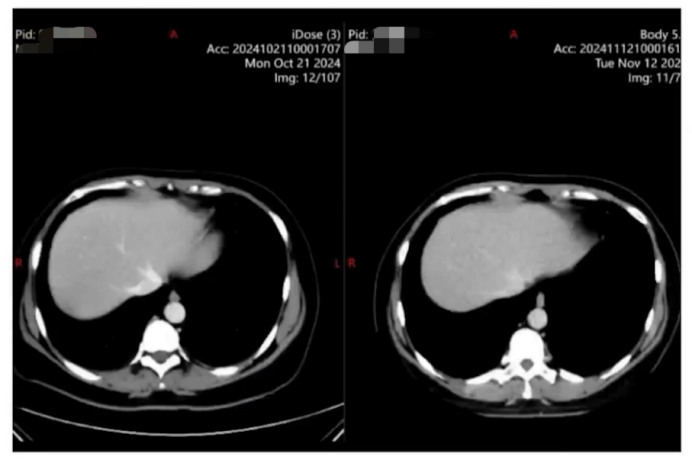

胸部CT:双肺多发微结节;腹部CT:提示肝右叶片状稍低密度影(4.2cm×5.6cm),肝脓肿可能。

经验性给予甲硝唑、米诺环素和头孢曲松治疗,覆盖院外未覆盖的可能病原体,同时复查腹部CT,显示肝右叶片状稍低密度病变较前增大,遂再次行经皮肝穿刺引流,送检肝组织NGS化验,但结果未提示特殊病原体。初步考虑肝内感染指标阴性,结核、真菌相关检查阴性,寄生虫相关化验再次复查也无阳性结果。免疫方面,ANCA斑点法1:160阳性,但ANCA阴性,过敏原因无特殊提示。肿瘤方面,外周血涂片提示嗜酸性粒细胞升高,未见到异型细胞,肿瘤标志物CA724轻度升高,其他包括AFP均为阴性。

追问患者流行病学史,患者有食用凉拌蔬菜情况,且曾长期在外卖平台购买泰国菜,多为蔬菜沙拉。明确诊断后,给予特效药三氯苯达唑治疗,患者服用两天后体温持续正常,稳定1周后出院。出院后随访,嗜酸性粒细胞呈进行性下降趋势,体温保持稳定正常,腹盆CT复查显示病灶缩小。